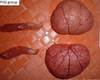

Pathogenesis (img)

Grain overload, rumenal acidosis, mucosal damage, opportunistic fungal infection, vasculitis, ischemia and mucosal ulceration